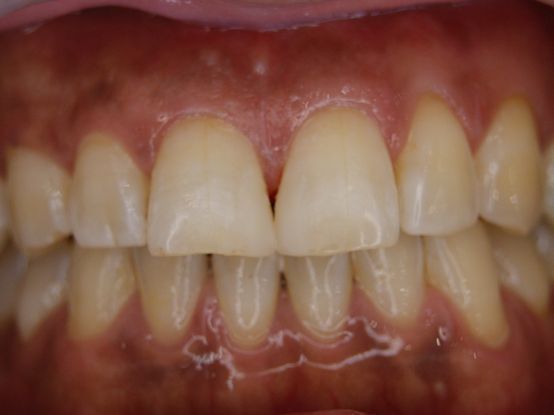

フィステル(瘻孔)があって、変色している症例。根管治療をすると、フィステルは消失。

DSC00513.JPG

DSC00520.JPG

レントゲン写真がこちら。根管治療&根管充填(この場合キャナルス&ガッターパーチャ)後。

で、漂泊してCR充填すればきれいに出来上がり。